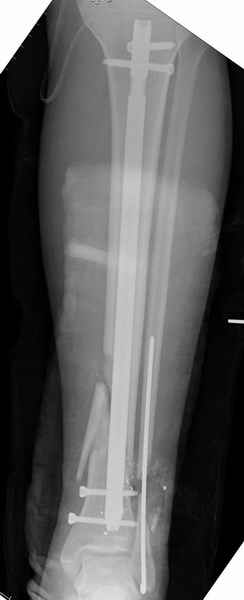

На снимках варианты фиксации малоберцовой:

№ 1 двух лодыжек

Фиксация переломов малоберцовой: пластина, интрамедуллярные конструкции или tension band technique.

Если перелом низкий и поперечный, делаю интрамедуллярно, спицей или интрамедуллярным штифтом, при косых переломах пластина (antiglide technique), при пользовании аппарата Илизарова спицу провожу через тибиа-фибула.